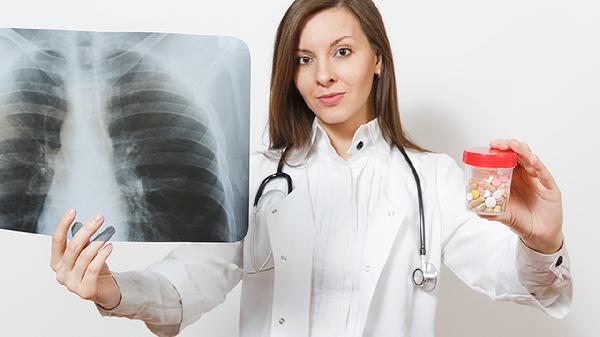

这些信号就像身体的摩斯密码,越早破译越能掌握主动权。特别要提醒长期接触厨房油烟、有肺癌家族史、50岁以上人群,每年做一次低剂量螺旋CT筛查。记住,早期肺癌的五年生存率可达80%以上,关键就在于及时发现这些不起眼的身体变化。下次身体出现这些异常,别急着贴膏药或吃润喉片,先给肺部做个全面检查更稳妥。